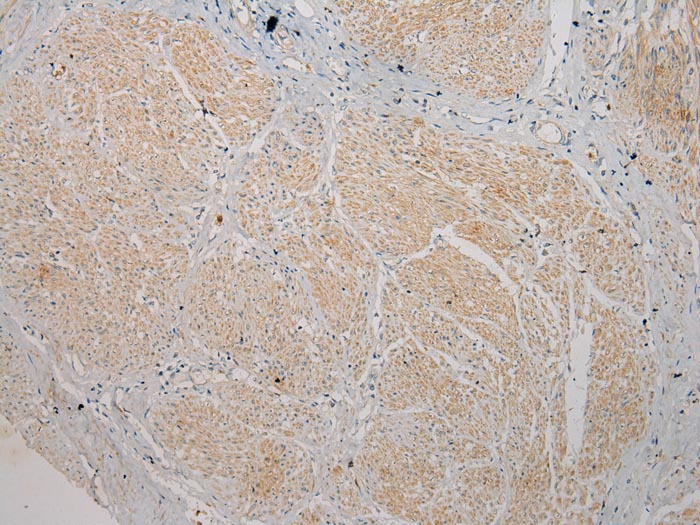

Immunohistochemical analysis of paraffin-embedded Human Prostate cancer tissue using #40270 at dilution 1/100.